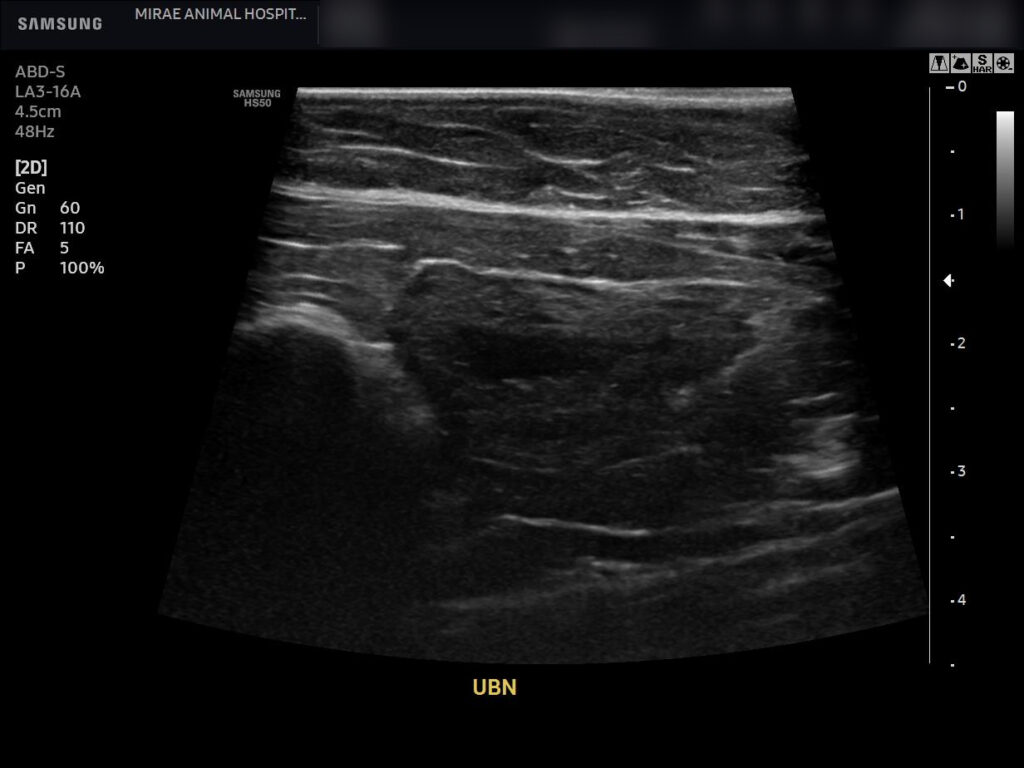

환자의 치료 후 복부 초음파 사진/ 출처: 미래동물의료센터

두 영상 검사 모두 이전에 심하게 팽대되어 있던 방광이 뚜렷하게 줄어든 소견이 확인되었으며 요도 폐색 소견 없이 자발 배뇨가

원활하게 이루어지고 있음을 확인할 수 있었습니다.